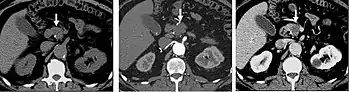

CT angiography (CTA) is highly effective for evaluation of the arterial system, and has largely replaced conventional angiography due to the lower risk profile and ability to survey the entire abdomen. Images are acquired after a rapid bolus of intravenous contrast material (3-7 cc/s) during the arterial phase (15–35 seconds after injection) when the concentration of contrast material in the arterial system is high (figures 3). Images are usually acquired using narrow collimation (<1 mm) and can be retrospectively reconstructed using dedicated 3-dimensional workstations and software. CTA is commonly used in the head and chest in the evaluation of pulmonary emboli, aneurysms, vascular malformations, dissection, bleeding and ischemia. Indications for early arterial phase imaging include: evaluation of aneurysms or dissections (cerebral, aortic, etc.), hepatic, splanchnic or renal arterial anatomy, and arterial imaging in liver or kidney transplantation. Single phase arterial imaging is often used in the evaluation of trauma patients either a complete chest/abdomen/pelvis examination with arterial phase imaging of the chest and portal venous phase imaging of the abdomen/pelvis or just a portal venous phase of abdomen and pelvis depending on the mechanism and severity of the trauma. CTA is also commonly performed in the abdomen and pelvis for evaluating vascular malformations and in the evaluation of bleeding. Mesenteric ischemia can also be evaluated using CT angiography. CTA of the abdomen and pelvis is often performed in combination with a CTA for evaluating the extremity vasculature.